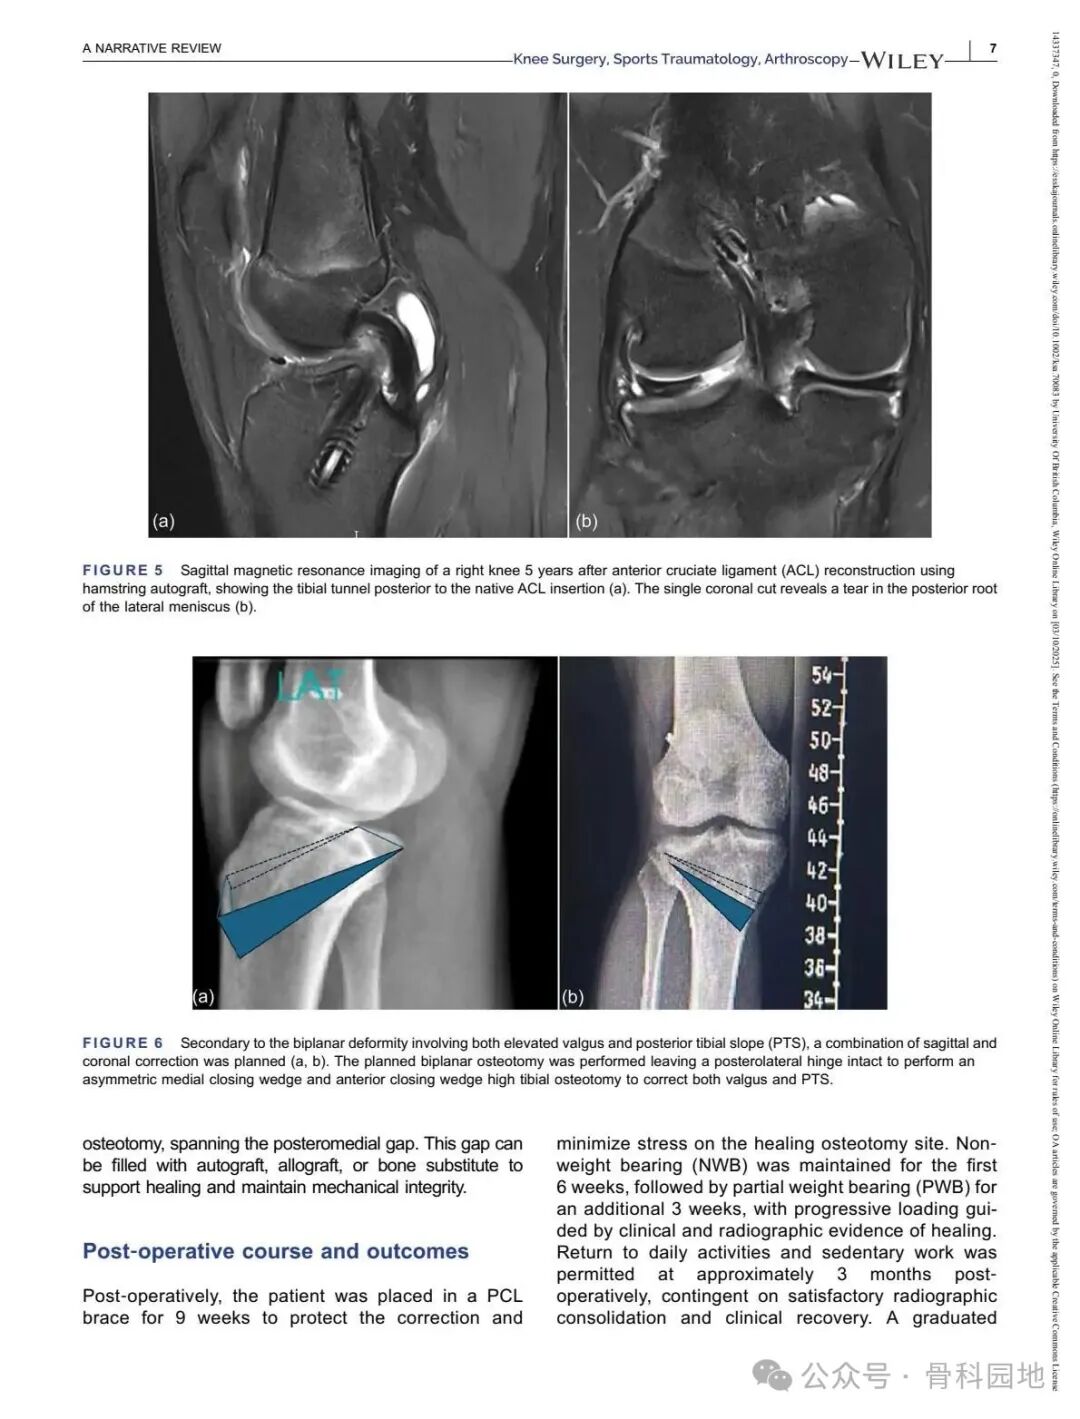

Although conventional high tibial osteotomy (HTO) primarily addresses coronal plane malalignment, the importance of sagittal plane alignment—specifically the posterior tibial slope (PTS)—cannot be overlooked in the setting of cruciate ligament insufficiency. Combined coronal and sagittal plane deformities are relatively rare and present unique surgical challenges. This narrative review summarizes the available literature and presents technical tips for managing complex biplanar deformities through a case‑based discussion of different techniques.